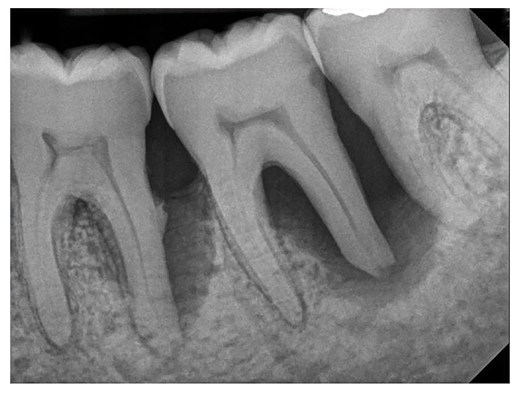

The patient's periodontal disease improved with initial nonsurgical periodontal therapy that involved scaling and root planing. This initial treatment was followed by only SPT every 3 months. Despite treatment, residual deep periodontal probing depths remained, so a decision was made to maximize improvements with nonsurgical therapy and to reassess as needed to determine whether surgical intervention was appropriate. After almost 5 years of SPT and good patient compliance with plaque control and supportive care, the periodontium was stable. Because of the resulting bone formation and improvements in clinical attachment levels (Figure 7 through Figure 13), it was determined that periodontal surgical intervention was not necessary.

In the case report presented, treatment with nonsurgical therapy for 5 years effectively halted destruction and led to bone regeneration and improved clinical attachment levels. Although the primary etiology of periodontal disease is well documented, secondary etiologic and contributing factors are numerous.16 After initial therapy in the current case, there was radiographic evidence of a hypercementosis-like lesion on the distal root of tooth No. 19 (Figure 7 through Figure 10). Hypercementosis is a nidus for plaque accumulation leading to disease progression; however, the presence of this lesion did not explain the disease severity observed for tooth No. 18. Chronic periodontitis is the most widespread form of periodontal disease, and nonsurgical periodontal therapy is the most common type of therapy.17 Scaling and root planning is the gold standard for periodontal treatment. When performed meticulously, they result in improvement of clinical parameters through changes related to tissue shrinkage, long junctional epithelium, new attachment, and in rare circumstances, regeneration.18 The use of nonsurgical periodontal therapy for treatment of periodontal disease requires that the timing for re-evaluation is customized for each patient. Because individuals heal at different rates, the overall medical condition, nutritional intake, environmental and social risks factors, local factors, and colonization of pathogenic bacteria of patients should be considered.7,8 Some patients cannot afford, or choose not to pursue, surgical periodontal therapy. For these patients, clinicians should delay surgical decisions until periodontal risk factors are addressed and nonsurgical efforts are exhausted.

(7.) Progressive improvement in bone quality, quantity, and morphology during each time period, especially in the furcation area of tooth No. 18, which shows a noticeable narrowing of the width of the bony defects, slight apical resorption of the distal root of tooth No. 18, and the encasing of residual cementum on the distal root of No. 19 by new bone formation. Periapical radiographs were taken of teeth Nos. 17, 18, and 19 on June 25, 2016, January 28, 2017, August 23, 2019, and September 4, 2020, respectively, the final of which was taken after almost 5 years post-initial scaling and root planing and alternating supportive periodontal maintenance.

Figure 7

(8.) Progressive improvement in bone quality, quantity, and morphology during each time period, especially in the furcation area of tooth No. 18, which shows a noticeable narrowing of the width of the bony defects, slight apical resorption of the distal root of tooth No. 18, and the encasing of residual cementum on the distal root of No. 19 by new bone formation. Periapical radiographs were taken of teeth Nos. 17, 18, and 19 on June 25, 2016, January 28, 2017, August 23, 2019, and September 4, 2020, respectively, the final of which was taken after almost 5 years post-initial scaling and root planing and alternating supportive periodontal maintenance.

Figure 8

(9.) Progressive improvement in bone quality, quantity, and morphology during each time period, especially in the furcation area of tooth No. 18, which shows a noticeable narrowing of the width of the bony defects, slight apical resorption of the distal root of tooth No. 18, and the encasing of residual cementum on the distal root of No. 19 by new bone formation. Periapical radiographs were taken of teeth Nos. 17, 18, and 19 on June 25, 2016, January 28, 2017, August 23, 2019, and September 4, 2020, respectively, the final of which was taken after almost 5 years post-initial scaling and root planing and alternating supportive periodontal maintenance.

Figure 9

(10.) Progressive improvement in bone quality, quantity, and morphology during each time period, especially in the furcation area of tooth No. 18, which shows a noticeable narrowing of the width of the bony defects, slight apical resorption of the distal root of tooth No. 18, and the encasing of residual cementum on the distal root of No. 19 by new bone formation. Periapical radiographs were taken of teeth Nos. 17, 18, and 19 on June 25, 2016, January 28, 2017, August 23, 2019, and September 4, 2020, respectively, the final of which was taken after almost 5 years post-initial scaling and root planing and alternating supportive periodontal maintenance.

Figure 10